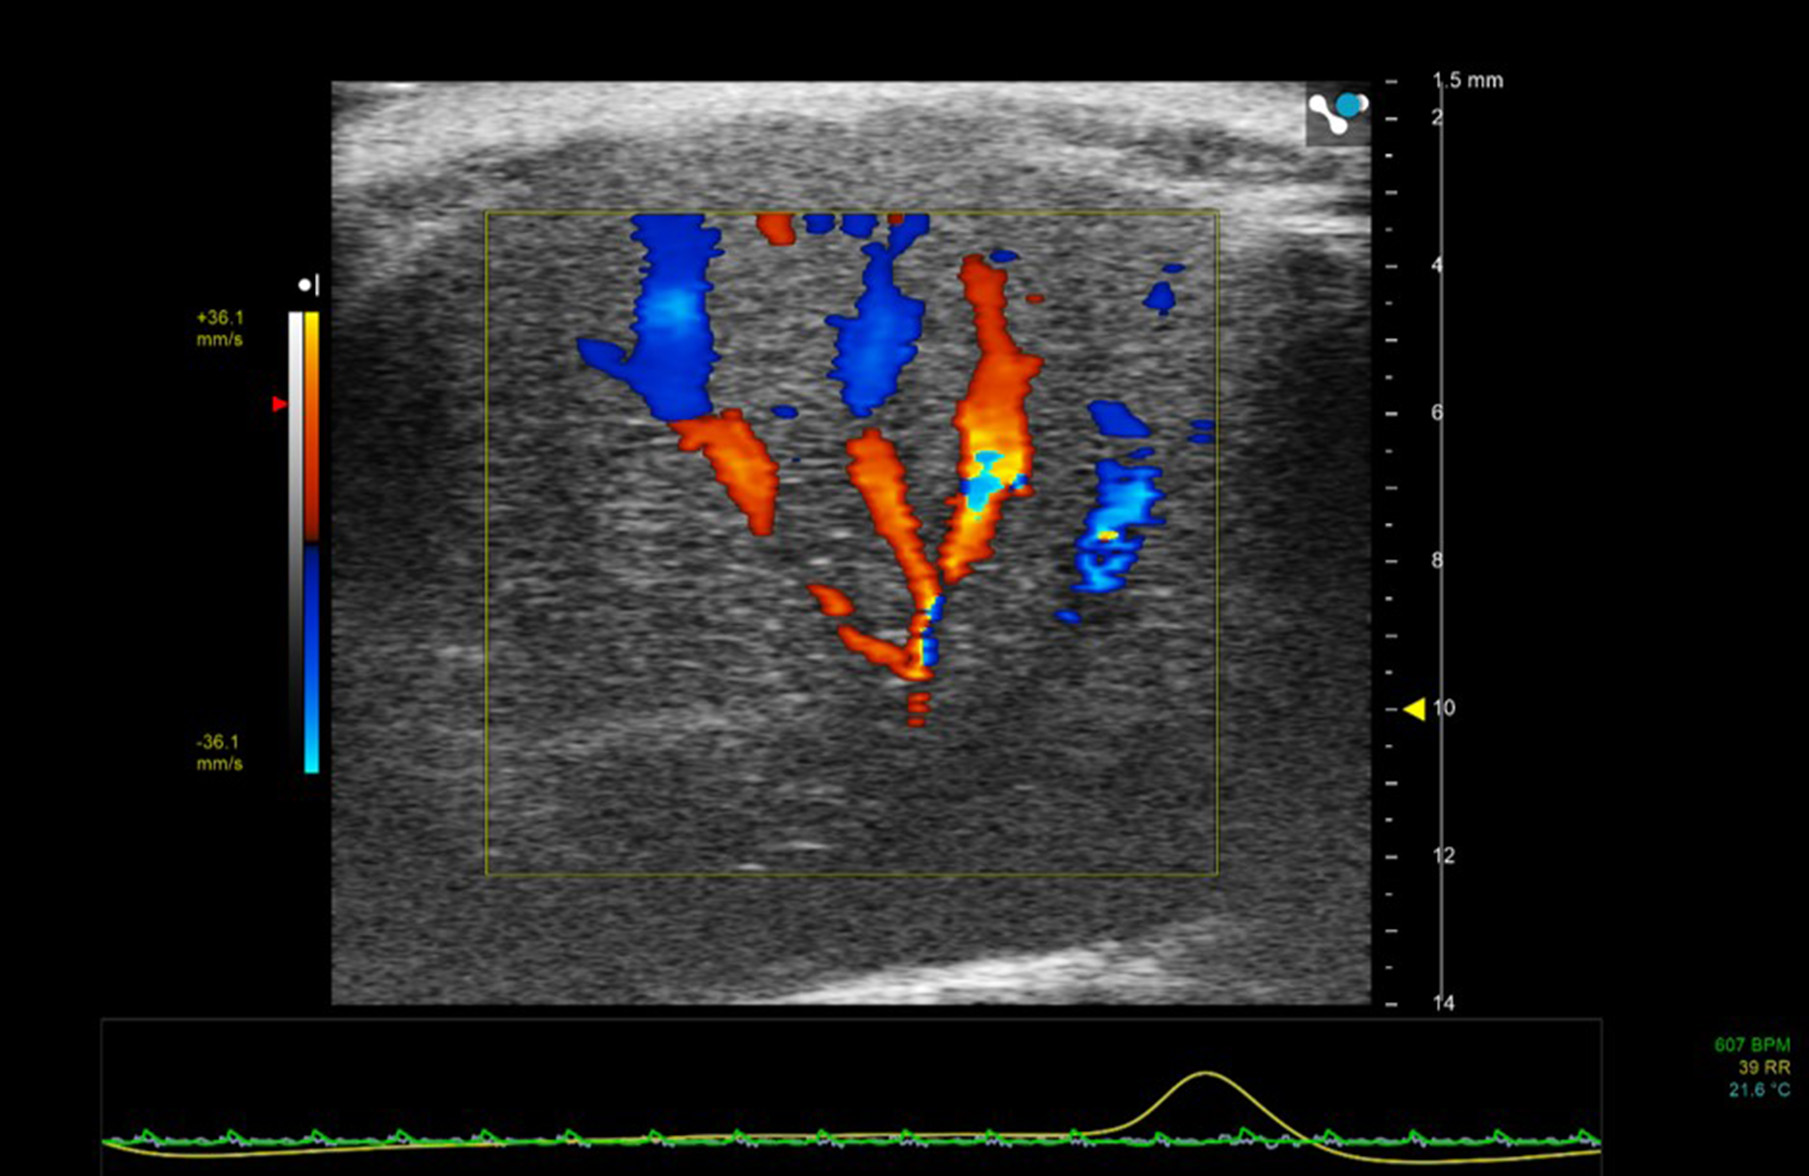

Color Doppler

In Color Doppler mode, the mean velocity of scatterers (red blood cells) within a pre-selected region-of-interest are color-encoded and superimposed on the gray-scale B-mode image. In clinical applications blood moving away from the transducer tends to be encoded in shades of blue and blood moving toward the transducer in shades of red. For preclinical applications, color Doppler is especially useful for the rapid location of vessels (Figure 5).

FIGURE 5

www.frontiersin.org

Figure 5. Color Doppler region of interest superimposed on 2D B-mode image of mouse liver. Color Doppler shows the vessel network—blue indicating movement of blood away from the transducer and red toward the transducer.